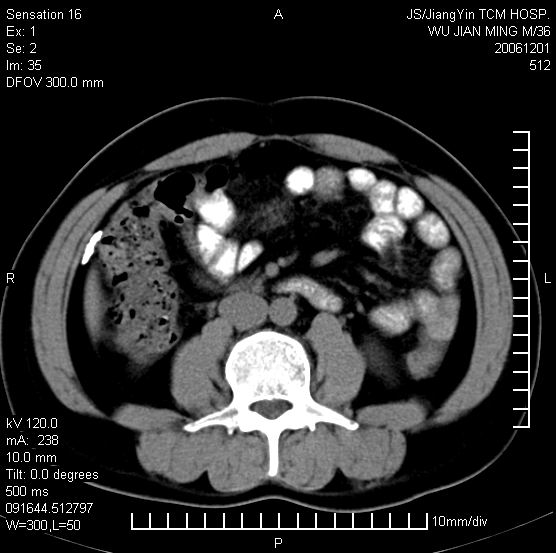

以下是引用dyqct在2006-12-1 21:17:00的发言:[br]左心缘旁及后肋膈窦区见巨大椭圆形混杂密度肿块,周围见大小不等斑片状钙化,内部无强化,周围包膜轻度强化,心脏明显受压变形,即明显占位效应,肿块广基与心包、膈相连。肝、脾内、肝门见多数小结节状钙化影。[br]考虑:1、左心缘旁及后肋膈窦区慢性包裹性胸膜炎(结核性);[br] 2、肝、脾及肝门淋巴结核已钙化。[br]

以下是引用zrs在2006-12-2 17:28:00的发言:[br]肺内、肝脾内虽有钙化,但不支持结核性胸胸膜炎包裹,而支持寄生虫感染![br][br]

以下是引用zyx168在2006-12-2 10:10:00的发言:[br][br]肝脾肺内多发钙化灶